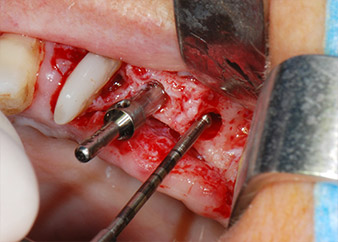

IImplant beds were prepared at sites 25 and 26 with rotary instruments, used in a contra-angle handpiece with a 20 : 1 transmission ratio with an updated powerful implant motor (Implantmed, W&H) (Fig. 8).

The final preparation next to the sinus was again carried out with a piezoelectric instrument (Piezomed, insert S2).

The implants (Restore, Keystone Dental, diameter 3,75 mm, length 8.0 mm) were placed with the implant motor (Figs. 11 and 12).